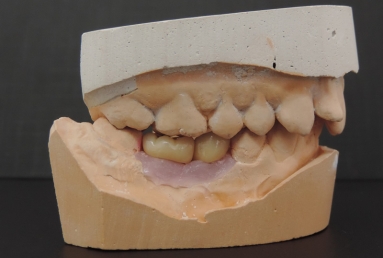

Initial situation: two missing teeth, second lower premolar and first lower molar. two dental implant are integrating in the mandibular bone for 4 months, then, gingival healing caps are applied for 3 weeks. an impression is taken for the dental lab in order to manufacture 2 porcelain fused to metal crowns. they will be screwed directly in the implant body.